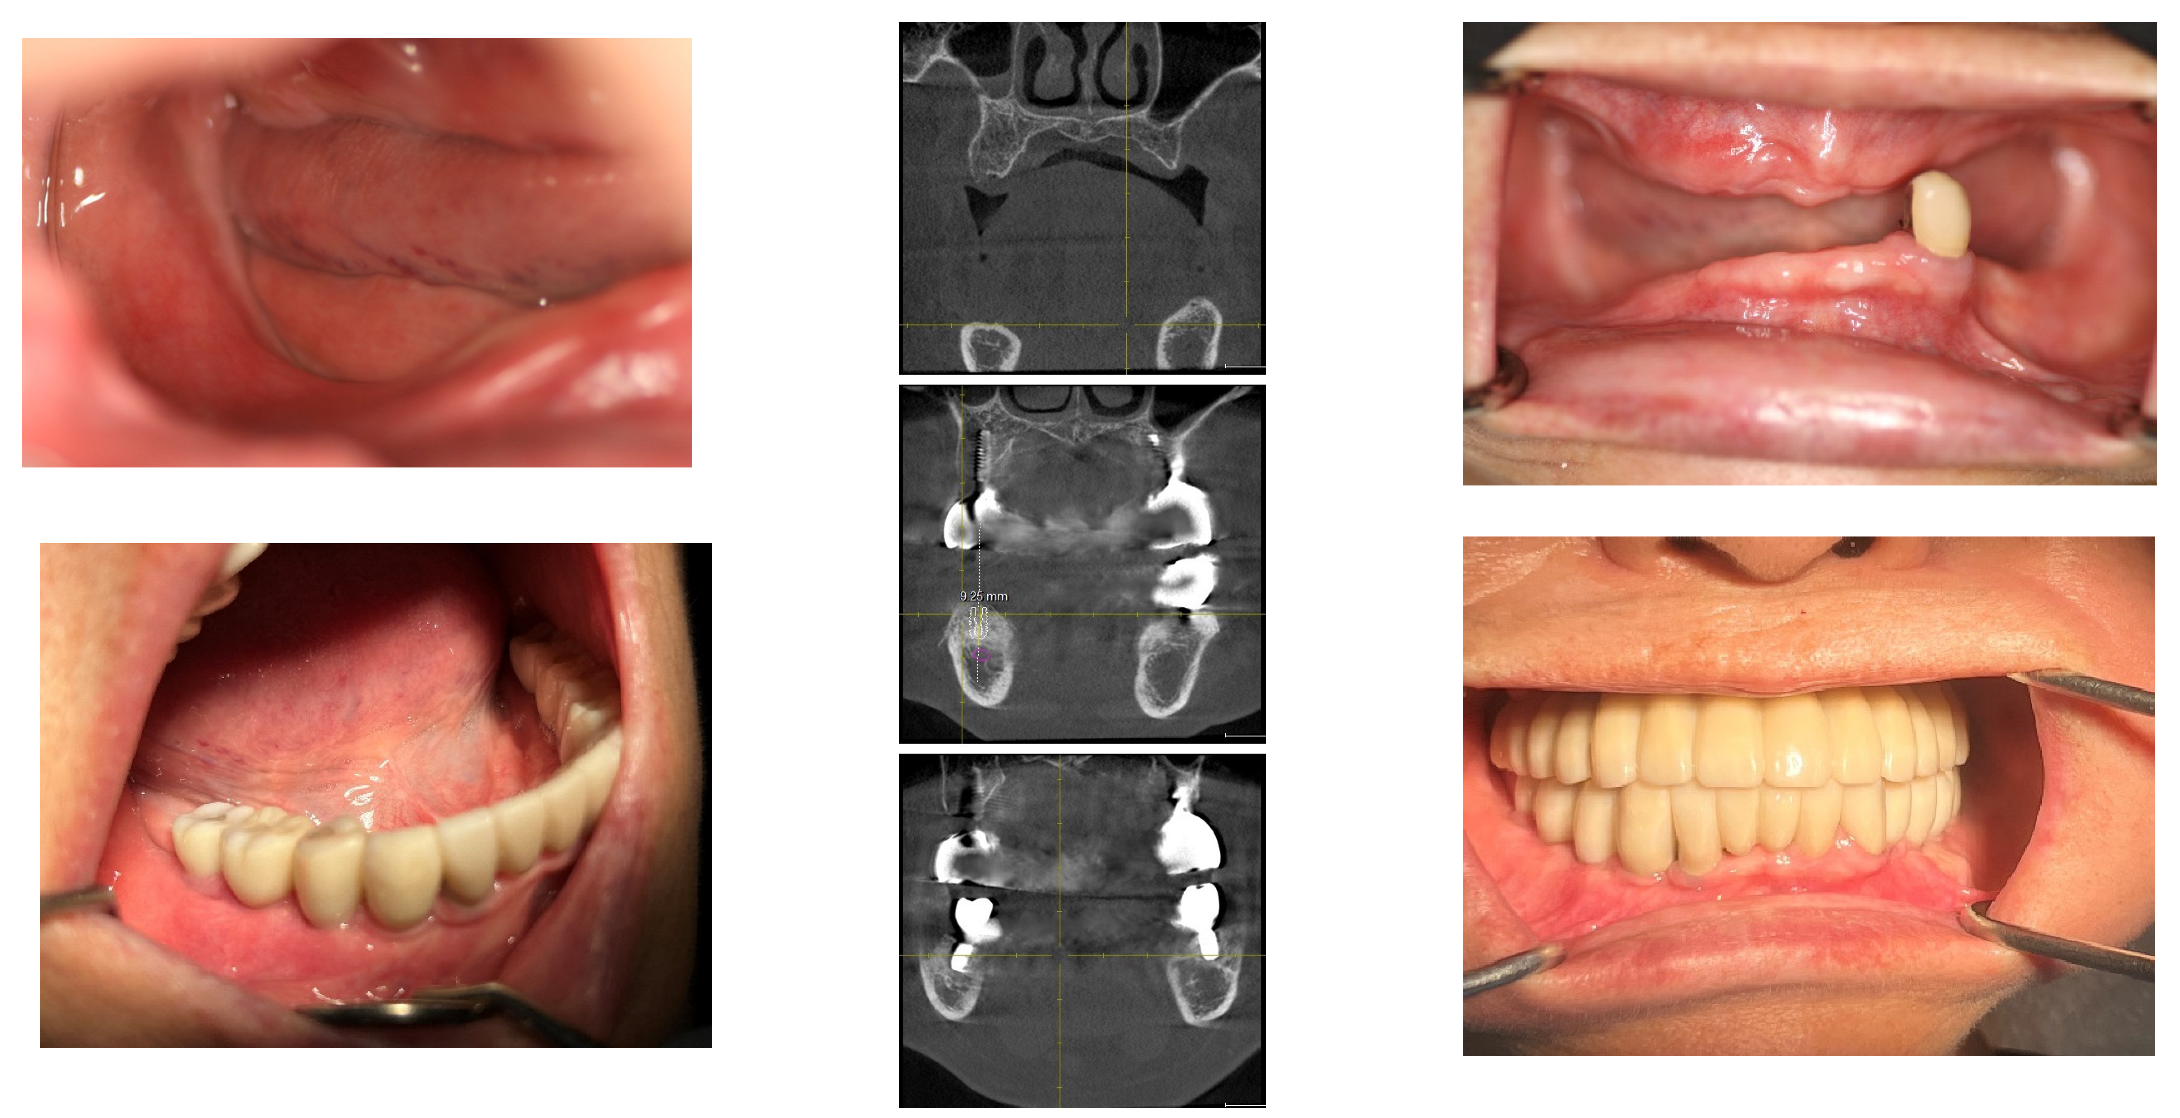

Initially, in April 2015, the heights at Points A and B were recorded as 1.3 mm and 2.5 mm, respectively. Subsequent to the first bone graft, facilitated by SITE (Self Inflating Tissue Expander), the heights increased to 7.1 mm at Point A and 7.6 mm at Point B by October 2015, resulting in vertical increments of 5.8 mm at Point A and 5.1 mm at Point B. Following the second bone graft, minor increases were observed in May 2016, with heights reaching 8.9 mm at Point A and 9.7 mm at Point B. By the day of implant prosthesis completion in May 2017, both Points A and B recorded a crestal height of 8.3 mm. These heights were then tracked annually, showing a marginal decrease of 0.1 mm at point B and 0.15 mm at point A from the prosthesis completion in May 2017 to 2024. Over a span of seven years, the overall decreases were 1.1 mm at Point A and 0.7 mm at Point B, deeming these results indicative of stable crestal bone changes (Figure 10, Figure 11 and Figure 12).

Figure 11. Panoramic X-ray images displaying the perioperative state along with the annual changes postoperatively.